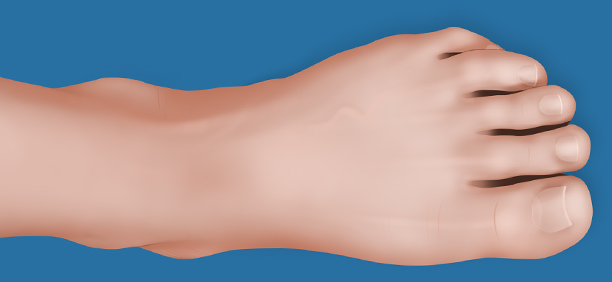

About the Interactive Foot & Ankle Chart

The San Luis Podiatry Group Interactive Foot and Ankle Chart will give you a better idea of the specific problem you may be experiencing due to discomfort in your foot. The possible conditions will lead you to a brief description of each pathology as well as link to a more medically focused, thorough discussion of that pathology.